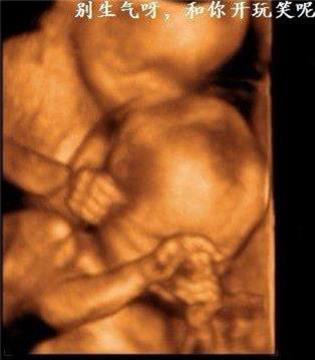

雙胞胎居然在打架   其實雙胞胎是心有靈犀的,看下面的這兩對雙胞胎,你就知道有多羨慕了 1、當這對雙胞胎從媽媽肚子裡生出來的那一刻,竟讓醫院所有人都震驚了!!原來這對雙胞胎竟是.手拉手出生的! 而當寶寶生下來的一刻,大家都驚呆了  爸爸都感動的哭啦 2、雙胞胎中的弟弟出生就沒呼吸,哥哥給他加油打氣,居然拉起弟弟的手 出生時,弟弟被查出了胸部感染,需要靜脈注射抗生素,這時哥哥竟然把手伸過來緊緊握住了弟弟的手。 「不要怕,哥哥保護你。」  就在護士向媽媽解釋如何治療的時候,突然哥哥伸出手去摸瓊斯,弟弟感覺到了就伸手來回應,然後他倆的手緊緊的握在了一起。這一幕太令人難以置信了!